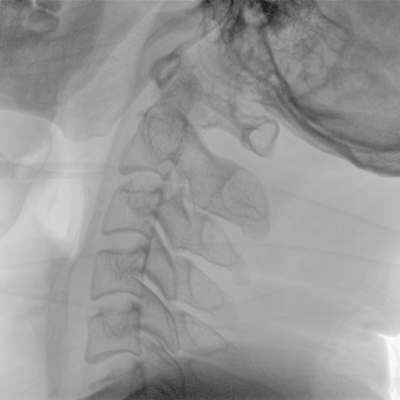

優質平板探測器、可靈活升降調節SID、獨特圖像處理系統、高品質濾線柵,大視野成像清晰不失真。

采用智能劑量控制技術,可根據不同體型和不同部位,準確調節投照劑量。使操作者在任何使用環境下,都能實現低劑量、診視圖像清晰的效果。